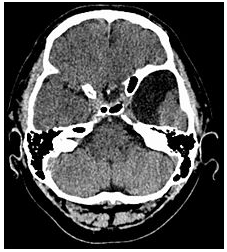

蛛網膜囊腫MRI表現CT 及 MRI 是蛛網膜囊腫最佳的診斷方法, 不但可以明確蛛網膜囊腫的部位、體積以及與周圍結構的關係,還能做出定性診斷。X線顯示蛛網膜囊腫鄰近骨質變薄、隆起或內板呈腦回壓跡樣凹陷等非特異性表現可作為輔助診斷。

1、CT 掃描顯示邊緣光滑、輪廓清晰、無鈣化、位於腦質外類似腦脊液密度的囊性病變 , CT 值為 4 ~ 8Hu , 周圍無水腫帶 , 造影劑無強化效應。毗鄰腦組織受壓,但一般多無中線移位。一些特殊部位如鞍上、四疊體的病變壓迫室間孔或導水管時可致腦室擴大、腦積水改變。

2、MRI 檢查蛛網膜囊腫的特點為 T1 加權圖像示低信號,T2 加權像示高信號,與腦脊液信號相同。MRI 檢查可以了解病變與腦實質、腦池的關係,建立三維圖像,制定手術方案。鞘內注射造影對鑑別蛛網膜囊腫與其它囊性病變或腦池畸形有重要意義。用泛影葡胺造影, 蛛網膜囊腫被造影劑襯托出一圓形充盈缺損。MR 相位對比電影法可以有效了解腦脊液流通動力學,可鑑別蛛網膜囊腫和蛛網膜下腔擴張,也可了解囊腫與蛛網膜下腔交通情況,較鞘內造影檢查具有無創、準確性高的優點。